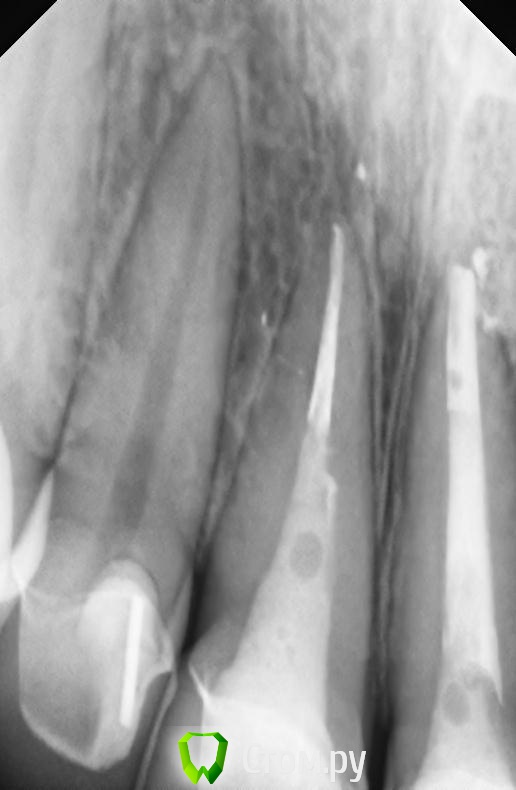

markoFFka Опубликовано 22 ноября, 2013 Автор Поделиться Опубликовано 22 ноября, 2013 Перелома нет? Есть сомнения по снимкуну меня этот же вопрос собственно и интересует.но на двойке с другой стороны,как мне кажется,тоже подобные полосы.вот снимок 12. Ссылка на комментарий

Kivilgar Опубликовано 23 ноября, 2013 Поделиться Опубликовано 23 ноября, 2013 Да нет,там точно не десна,контактные пункты хорошие ,просто снимок такой. Флосс проходит с щелчком, как положено.Тем более,что чувствительность при накусывании именно после пломбировки канала появилась.Подобные ощущения может давать пародонт а не десна. Это что на 21? http://s020.radikal.ru/i711/1311/27/3d119944ca54.jpg Ссылка на комментарий